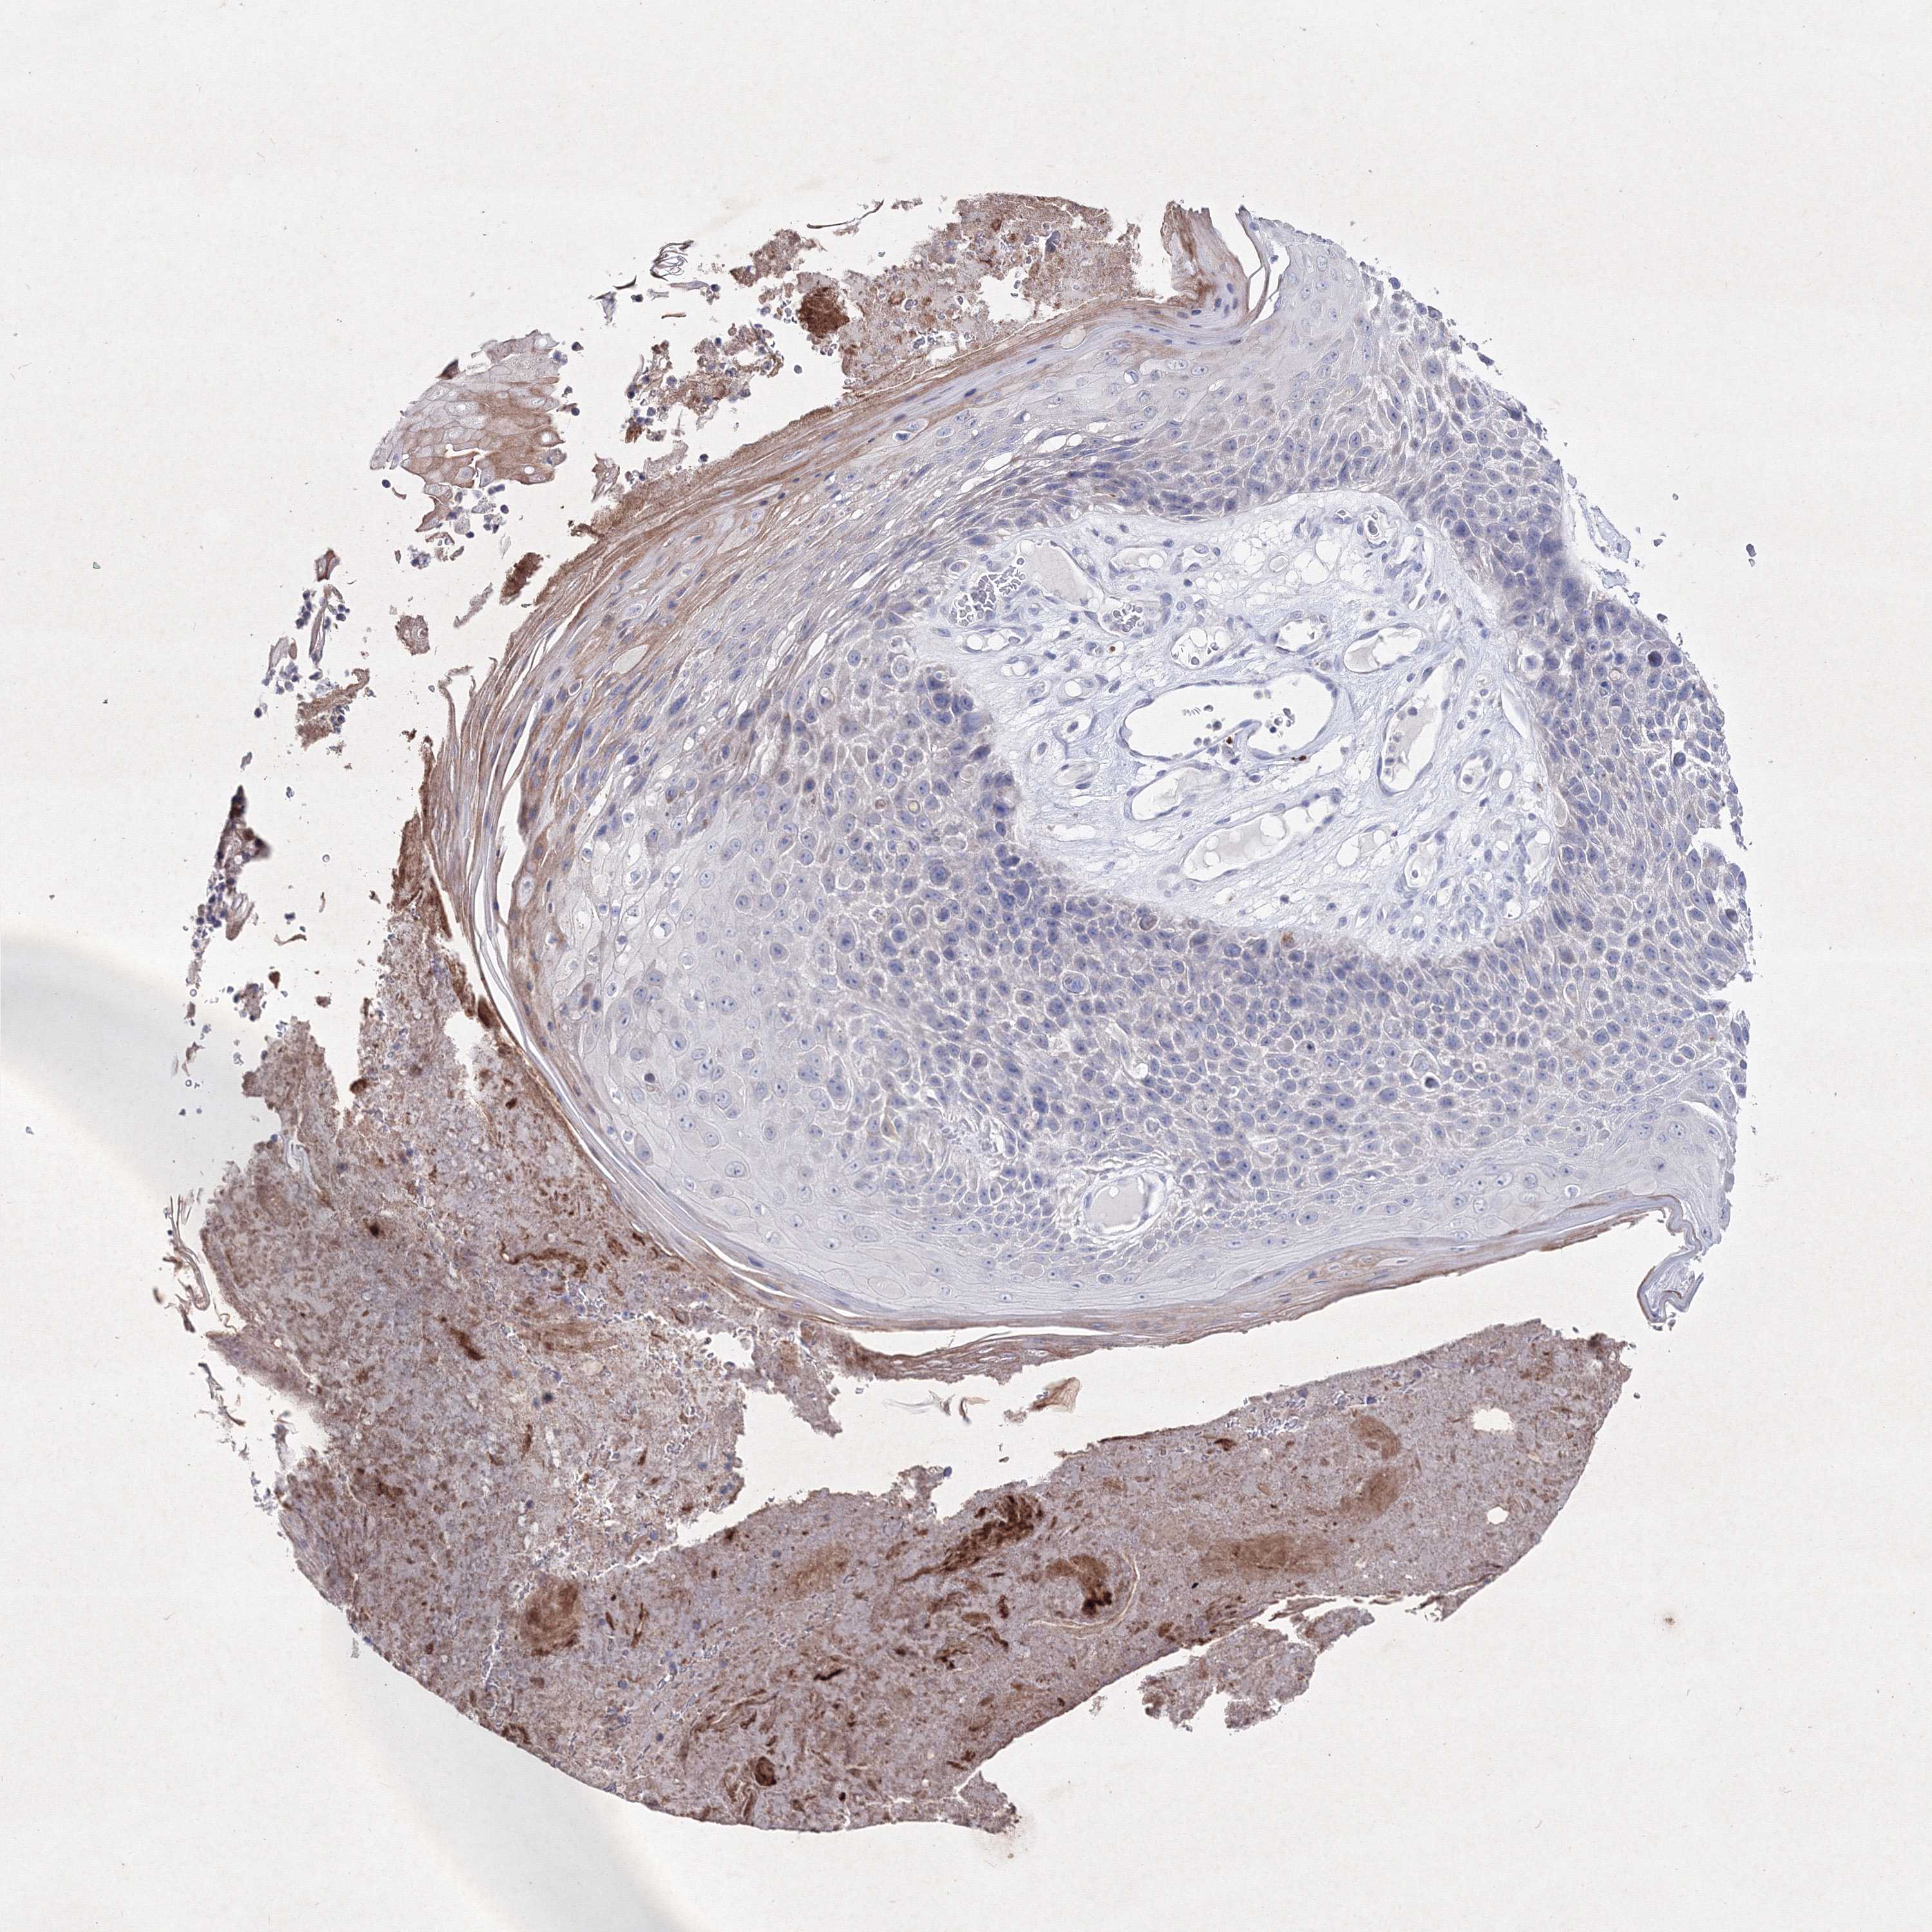

SKIN CANCER - Protein expressioni

A mouse-over function shows sample information and annotation data. Click on an image to view it in a full screen mode. Samples can be filtered based on level of antibody staining by selecting one or several of the following categories: high, medium, low and not detected. The assay and annotation is described here.

Antibody stainingi

Antibody staining in the annotated cell types in the current human tissue is reported as not detected, low, medium, or high, based on conventional immunohistochemistry profiling in selected tissues. This score is based on the combination of the staining intensity and fraction of stained cells.

Each image is clickable and will lead to virtual microscopy that enables deeper exploration of all samples and also displays staining intensity scores, fraction scores and subcellular localization as well as patient and tissue information for each sample.

Antibody HPA037659

Antibody HPA037660

Staining

High

Medium

Low

Not detected

Intensity

Strong

Moderate

Weak

Negative

Quantity

>75%

75%-25%

<25%

None

Location

Nuclear

Cytoplasmic/membranous

Cytoplasmic/membranous,nuclear

Basal cell carcinoma

Squamous cell carcinoma, NOS

Squamous cell carcinoma, metastatic, NOS